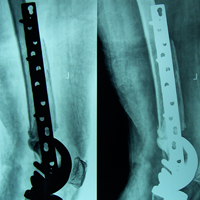

Case:14 Periprosthetic Fracture

60 years old patient with total knee replacement on left knee presented with open grade 1 injury. Debridement & slab given on emergency bases. Fixation with plate & screws done. Union was seen after 6 months.

Pre-Op AP

Pre-Op Lat.

Immdiate Post-op

1 and half months Post-op

2 and half months Post-op

3 and half months Post-op

4 and half months Lateral

6 Years Follow-Up